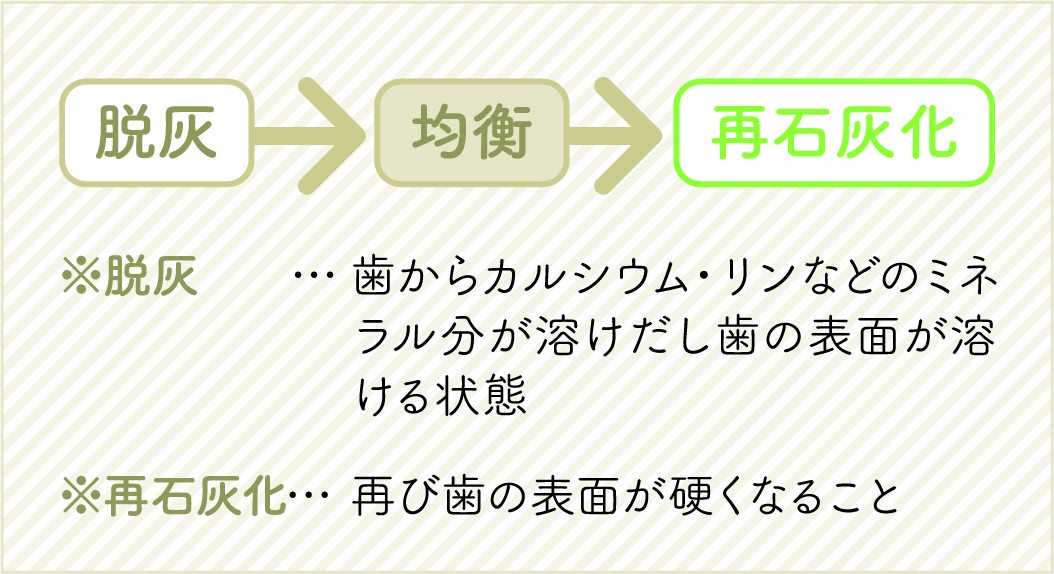

歯が溶けて、溶けるのが止まり、再び固まるという流動的な過程の病気です。

下の図を見ていただくとわかりやすいのですが、食べ物(糖)が口の中に入ると口腔内の細菌が糖をエネルギーにして、2~3分でプラーク(=歯の表面のネバネバした汚れ(歯垢))を酸性に傾け歯の表面を溶かし始めます。これが「脱灰」です。

その後、唾液の力で約20分~40分かけて歯の表面を元どおりに治していきます。これが「再石灰化」です。

ここで注目していただきたいのが時間です。脱灰は2~3分で始まるのに対して再石灰化には20~40分もかかってしまいます。

つまり、常にダラダラと食べてしまう(間食が多い)と再石灰化で歯の表面が元に戻る前に再び脱灰が始まってしまい、歯の表面がどんどん溶け、やがて虫歯になってしまうのです。

虫歯は脱灰・均衡・再石灰化という流動的な過程の病気であるとお伝えしてきましたが、最初の脱灰はこの酸耐性の低い部分から始まります。ですが、その後の再石灰化によって固まった部分は、酸耐性が高まります。そしてその際に微量のフッ素が存在するとより酸耐性が高くなるのです。

酸耐性が高まるというのは、酸によって溶けにくくなる、つまり虫歯になりにくくなるということです。

歯は脱灰と再石灰化を繰り返すたびに歯質の酸耐性が増し、成熟していきます。